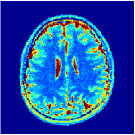

VI-E In-vivo experiments

Two sets of experiments were conducted here: first, we used the 2D and 3D acquisition sequences for scanning a healthy volunteer’s brain (real-world acquisitions). Figures 6 and 7 display the parametric maps reconstructed from 2D spiral and radial readouts. We computed the T1, T2 and proton density (PD) maps using baseline reconstruction algorithms ZF, VS, LR, FLOR, AIR-MRF and our proposed LRTV. While baselines use DM either for quantitative inference or also during reconstruction (i.e. AIR-MRF), we further compare the DM-free LRTV’s performance when cascaded to DM, KM and MRFResnet for quantitative inference. For the 3D spiral acquisitions we compared LRTV and its closest competitor VS in Figure 8. Outcomes from other tested algorithm are displayed in the supplementary materials (Figure S5). Since FLOR does not use dimensionality-reduction, our system ran out of memory during 3D reconstruction; hence results are not reported in this case.